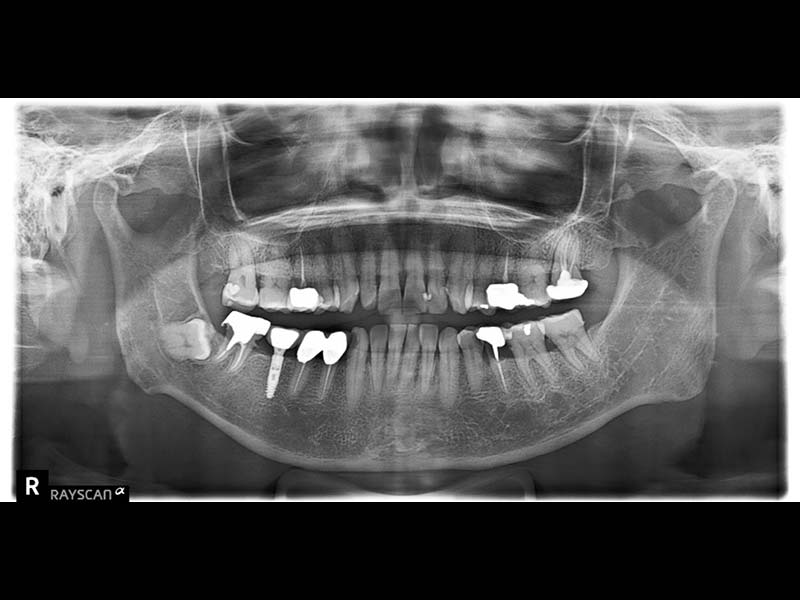

拍攝電腦斷層影像和口腔口掃並製作治療計畫